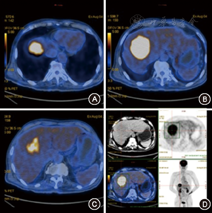

(1)病例特点:患者男性,69岁,因"胸闷不适5 d"于2015年8月6日就诊我院胸外科,正电子发射计算机断层显像(PETCT)提示:"肝右叶稍低密度肿块,考虑恶性可能大"(图1),以"肝占位"转入我科。既往史:否认肝炎病史。查体:无明显阳性体征。实验室检查:肿瘤标志物甲胎蛋白(AFP)、癌胚抗原(CEA)、CA19-9及其他生化检查未见明显异常。Child-Pugh分级为A级。B超及腹部增强CT均考虑恶性(图2,图3)。(2)治疗:手术行肝部分切除术,术中冰冻回报:考虑肝炎性肌纤维母细胞瘤。术后大体标本:呈黄白色、鱼肉状、质地较硬,似有包膜。(3)术后病理诊断为肝炎性肌纤维母细胞瘤。(4)预后:术后7个月门诊复查未见明显复发(图4),术后电话随访18个月未见明显复发表现,恢复良好。